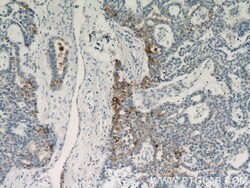

18507-1-AP IHC

Full details

Method: Other validation